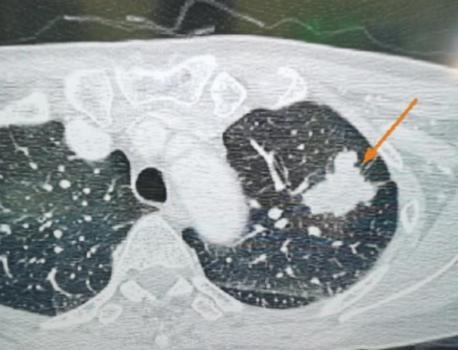

这位33岁的女性患者,体检发现右肺有2个磨玻璃结节,可以清楚地看到,这两个结节与